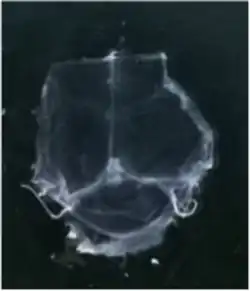

To visualize the dura mater using immunohistochemistry, the dura must first be fixed within the skullcap. It is prepared by cutting around the base of the skull (inferior to the post-tympanic hook) and removing the lower portion of the skull and brain. Following fixation, the dura can be dissected out of the skullcap as a single piece of tissue that can be utilized for histological analysis.[12]

Although several studies proposed the existence of lymphatic vessels in the dura mater, the presence of the meningeal lymphatic system was accepted in 2015, when two independent studies published by Louveau et al.[1] and Aspelund et al.[2] provided convincing data using novel methods. Louveau et al. noticed an unusual alignment of immune cells along the dural sinus using a meningeal whole-mount technique. Using lymphatic endothelial cell-specific markers and electron microscopy, the authors found that the immune cells were not inside blood vessels, but rather were organized inside lymphatic vessels within the meninges, a system of membranes that envelop the brain and spinal cord.[1]